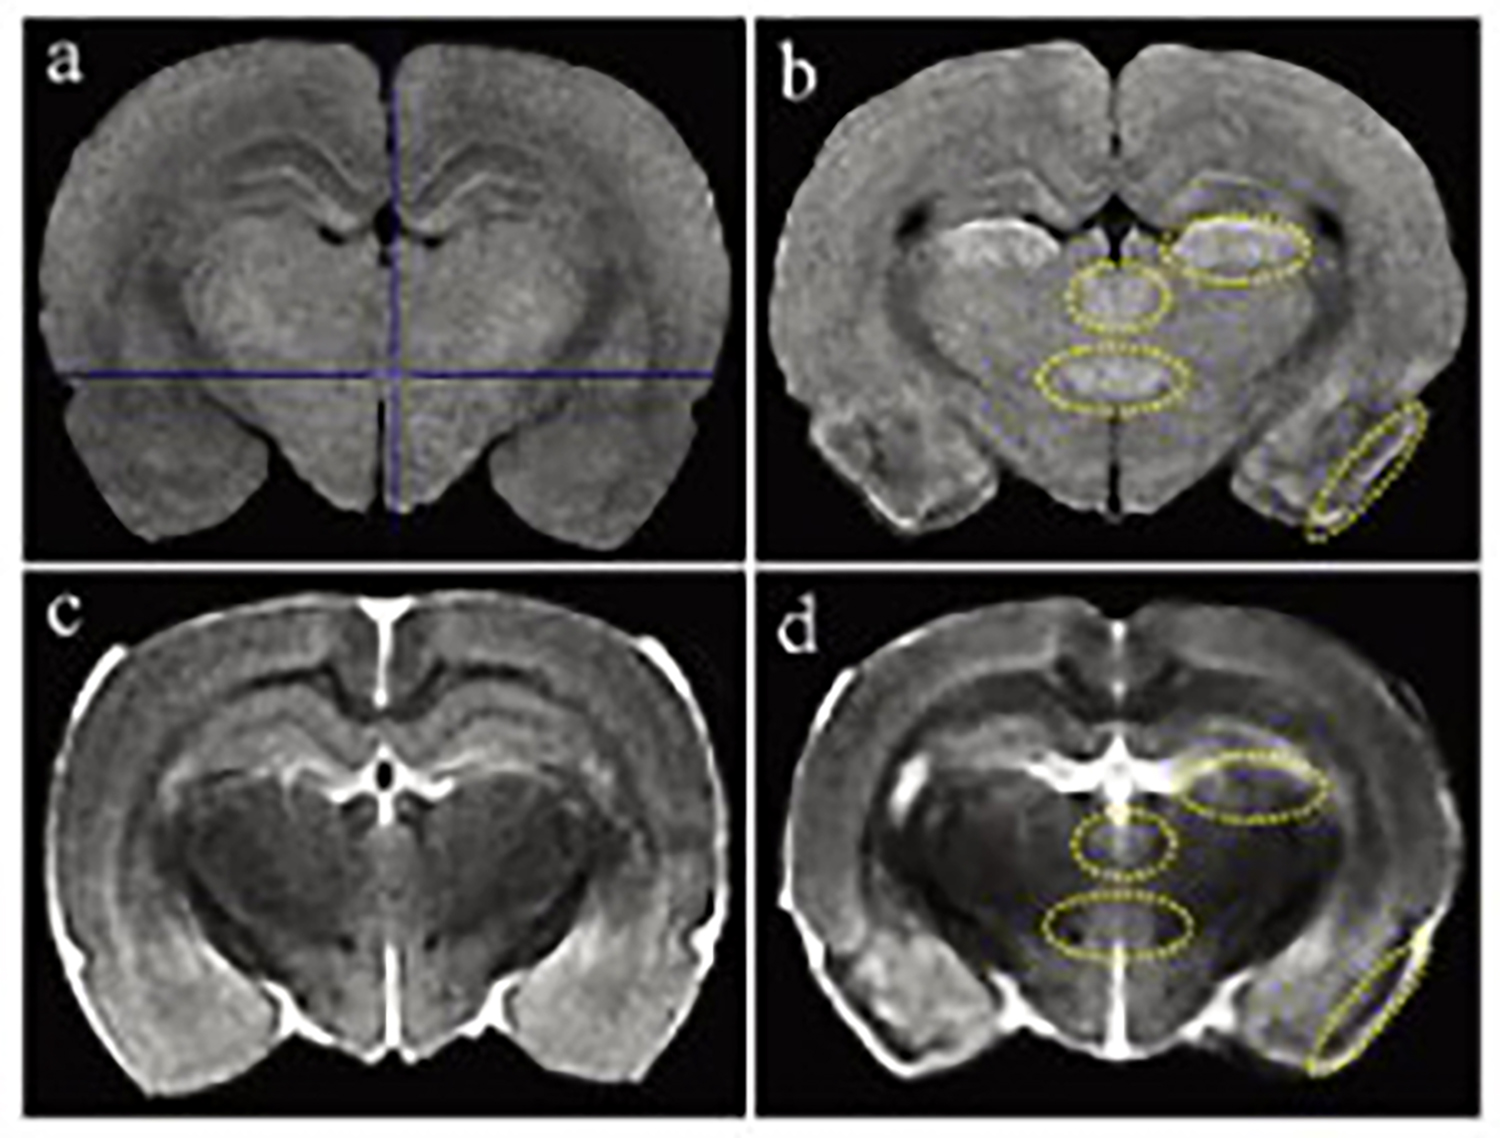

小动物磁共振成像系统在大鼠脑损伤评估中的应用

磁共振成像(MRI)广泛应用于临床前研究和药物开发,是一种强有力的无创性方法,可用于评估小鼠疾病模型的表型和治疗效果。

小动物磁共振成像(MRI)是一种强大的非侵入性工具,可用于检测临多种病变。